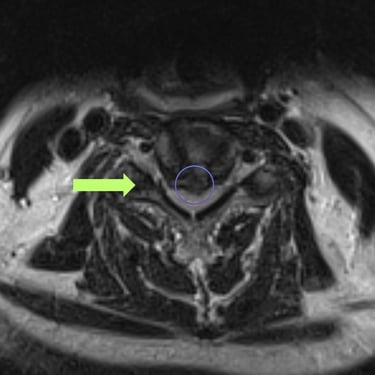

La hernia cervical es una causa frecuente de dolor en el cuello, hormigueo en los brazos y debilidad muscular. Cuando el tratamiento conservador no alivia los síntomas, la cirugía de discectomía cervical con artrodesis (ACDF) se convierte en una excelente alternativa. Este procedimiento consiste en retirar el disco dañado que comprime los nervios y reemplazarlo con un injerto o prótesis que estabiliza la columna. La ACDF ofrece alta tasa de éxito, mejorando el dolor, la fuerza y la calidad de vida. Gracias a técnicas modernas y una recuperación controlada, muchos pacientes vuelven rápidamente a sus actividades habituales.